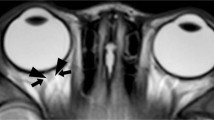

Subjective analysis of the optic nerves was limited to children without optic pathway glioma. Using T1-weighted 3-D MPRAGE sequences, transaxial and coronal images of the optic nerves were cropped so that the optic nerves were visualized from the orbital apex to the globe. These steps prevented the reviewer from discerning the NF1 diagnostic status of the subject. The subjective assessment of optic nerve tortuosity was performed by a pediatric neuroradiologist with 13 years of experience (R.C.M.). Scans were scored on a three-point scale: normal (0), intermediate tortuosity (1) and marked tortuosity (2) (Fig. 3). After the scans were scored, the images set was randomized and recoded with new scan IDs and a second subjective analysis was performed to assess test-retest reliability of the subjective interpretation. The retest analysis was completed with the same radiologist (RCM) and the same equipment 1 month after the original assessment.

Subject axial MRI scans. Subjective optic nerve tortuosity scores were determined by a radiologist (R.C.M.) on a three-point scale (from 0 to 2). a Optic nerve with a score of 0 (normal) in a 4-year-old girl. b Optic nerve with score of 1 (intermediate tortuosity) in a 2-year-old boy with NF1. c Optic nerve with a score of 2 (marked tortuosity) in a 5-year-old boy with NF1

In an effort to provide more objective methods for defining optic nerve tortuosity, Armstrong and colleagues [10] employed six radiographic features to independently assess MRI scans on individuals with NF1 whose optic nerves were suspected to be tortuous. The two most reliable features were (1) lack of congruity in greater than one coronal section and (2) dilation of the subarachnoid space surrounding the anterior portion of the optic nerve. The latter feature was highly specific and sensitive, but exhibited 64% concordance among three experienced neuroradiologists. The criterion used in this method is still relatively subjective, and thus limited in its utility for distinguishing normal from tortuous optic nerves. The method used in our study is both quantitative and reproducible, making it more easily translatable to future clinical studies.